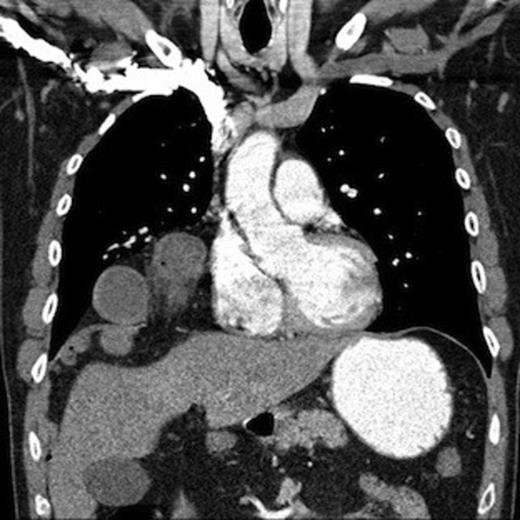

An unusual gas pattern was noted in the right lower zone, raising the suspicion of a small bowel diaphragmatic hernia, perhaps through the Foramen of Morgagni. Following initial resuscitation the patient underwent a CT scan. This confirmed a hernia through the mid part of the right hemi-diaphragm, containing omentum and loops of small bowel. (Figure 2)